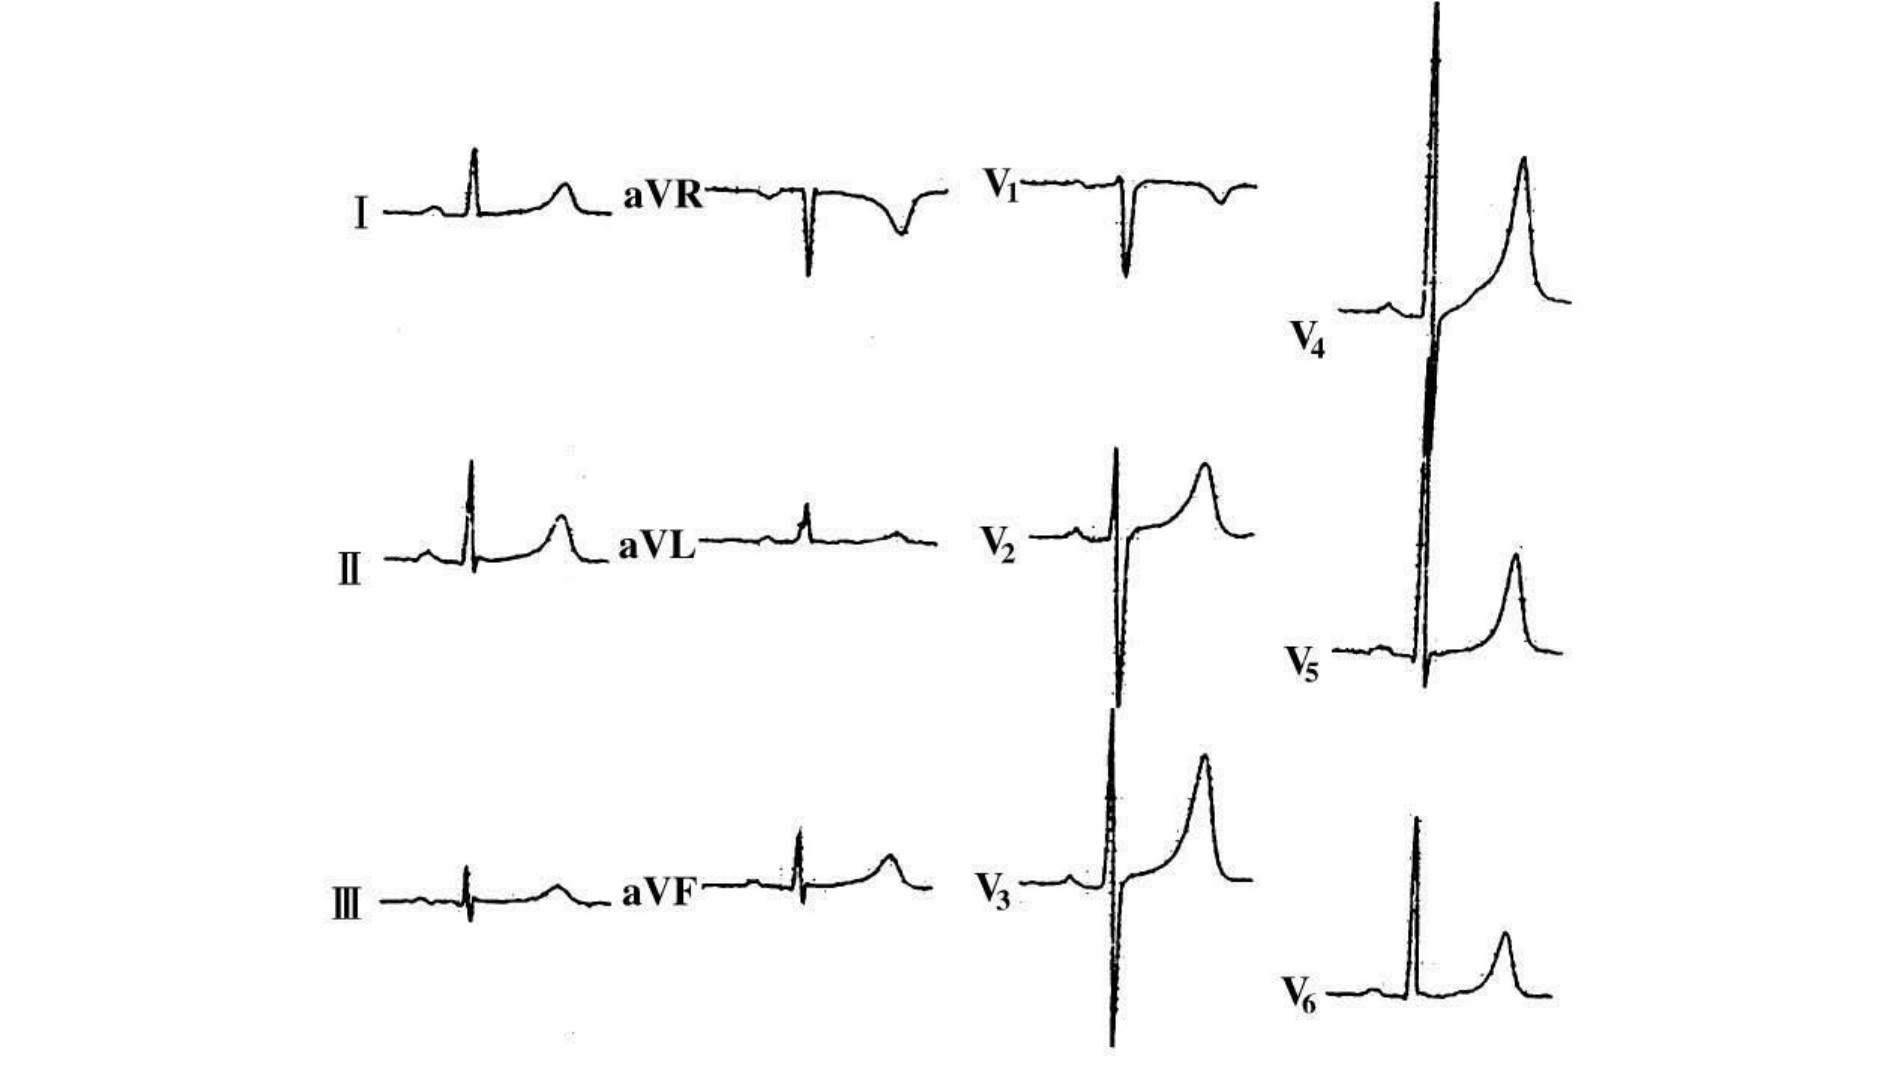

1.左心室肥大 劳损长期高血压可增加左心室后负荷,使左心室肥大劳损(图17-13)。

图17-13 肾功能不全,左心室肥大

男性,51岁,高血压,糖尿病,肾功能不全,心功能不全。窦性心律,心率99次/min,P-R间期0.14s,QRS时限0.98s,Q-T间期0.37s,V2导联S波为4.3mV,V5导联R波为3.0mV,V6导联R波为3.9mV。V6导联ST下降0.10mV,Ⅰ、aVL、V6导联T倒置,左心室肥大